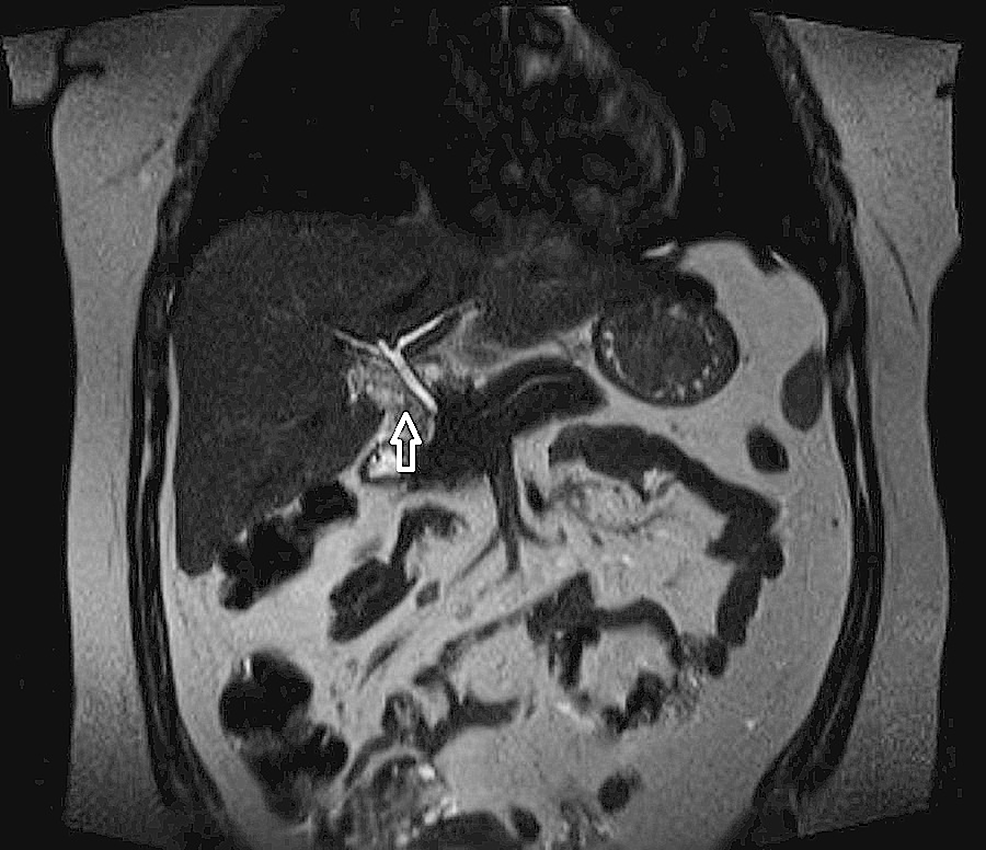

fig1:Hepatic Haemangioma Masquerading as the Gallbladder ...

fig1:Hepatic Haemangioma Masquerading as the Gallbladder ... from openi.nlm.nih.gov